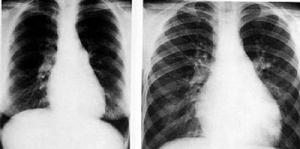

脫屑性間質性肺炎 X線表現,兩肺有對稱性磨玻璃模糊陰影,在肺底部最顯著。亦有呈三角形模糊陰影,從肺門向兩側肺底伸展,有時並發自發性氣胸或胸水。

脫屑性間質性肺炎 X線表現兩肺有對稱性磨玻璃模糊陰影在肺底部最顯著亦有呈角形模糊陰影,從肺門向兩側肺底伸展有時並發自發性氣胸或胸水。

肺功能檢查顯示限制型改變伴DLCO降低,動脈血氣顯示低氧血症。胸部X線在多達20%病例可正常,如有異常時,其嚴重程度低於間質性肺纖維化。HRCT示斑片狀,胸膜下的毛玻璃樣陰影。經支氣管鏡或開胸作肺活檢,可以確定診斷。

肺功能檢查顯示限制型改變伴DLCO降低,動脈血氣顯示低氧血症。胸部X線在多達20%病例可正常。如有異常時,其嚴重程度低於間質性肺纖維化。HRCT示斑片狀,胸膜下的毛玻璃樣陰影。